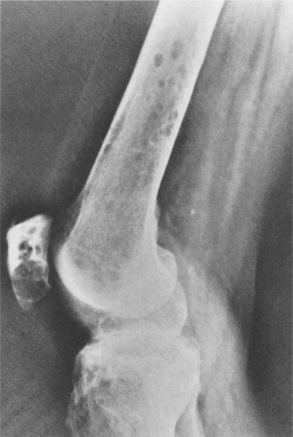

Anyone suspected of having Ewing’s sarcoma is staged for both local and metastatic disease. Radiographs show an obvious lytic process with a moth-eaten appearance involving a diffuse area of bone (Fig. 26-15). As mentioned, an onion-skin formation may be seen, which is due to layers of reactive bone (see Fig. 26-14). On radiographs the appearance may not differentiate this lesion from osteomyelitis or osteosarcoma.

Figure 26-15 Ewing’s sarcoma. A, A mixed lytic-sclerotic lesion in the femur of a child with periostitis that is amorphous and sunburst that is characteristic of Ewing’s sarcoma. B, This is a predominantly sclerotic process with large amounts of sunburst periostitis in the diaphysis of a femur that, on biopsy, was found to be Ewing’s sarcoma. (From Helms C: Fundamentals of skeletal radiology: benign cystic lesions, Philadelphia, 1989, WB Saunders.)